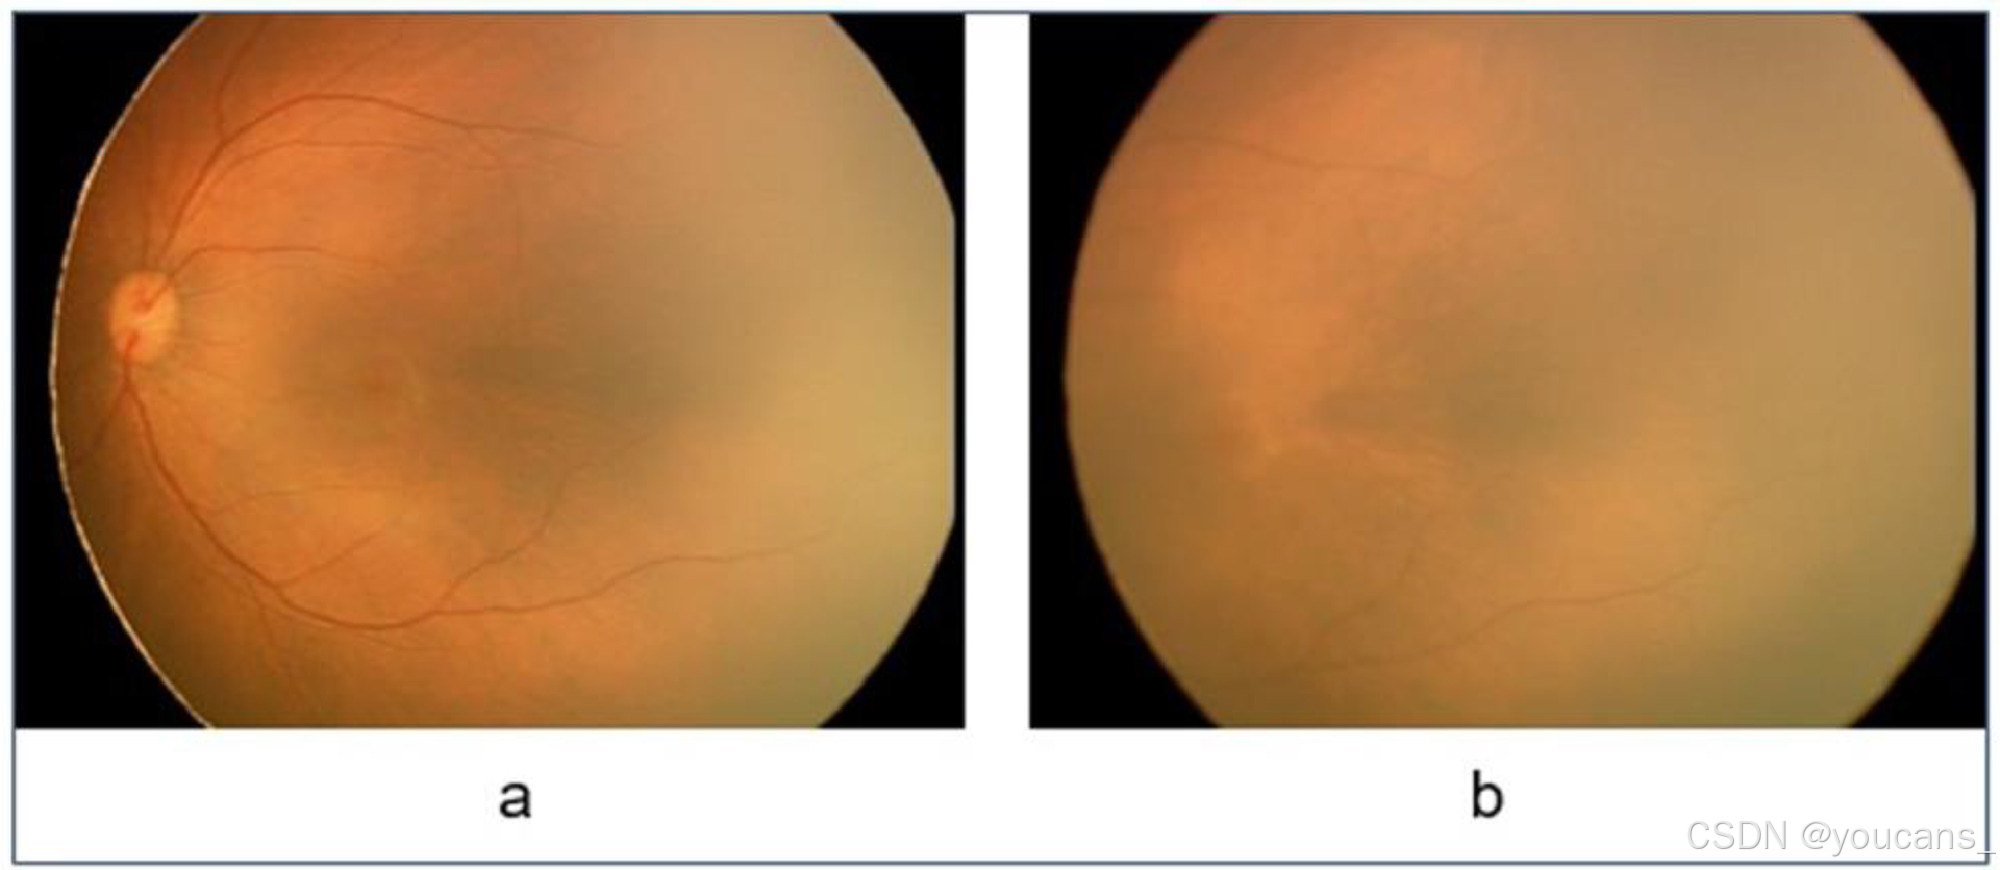

HVDROPDB数据集由早产儿的后部视图和颞部视图的眼底图像组成,如图1 和图2 所示。图1a 和2a 显示了视网膜后部图像(从视网膜的后方拍摄的图像),图1b 和2b 显示了视网膜颞部图像(从视网膜的侧面拍摄的图像)。

图1:RetCam图像(a)后视图,(b)颞部视图。